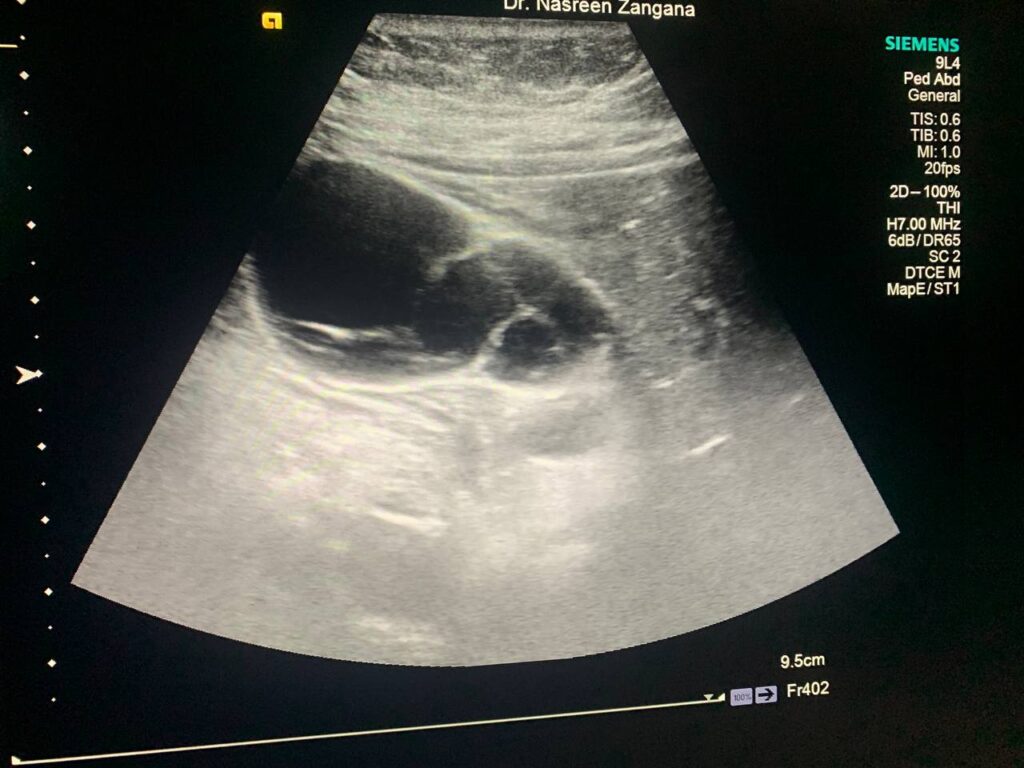

U/S : Gall bladder : distended , contain stone 9mm , full with heterogenous fluid , contain multiple honeycomb septations , also associated with pericholecystic edema 3.5mm , picture mostly of acute on chronic cholecystitis , please for further study normal common bile duct